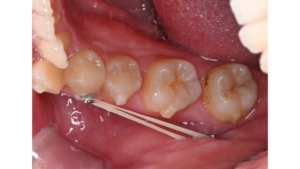

アタッチメントの装着: 歯の表面に、目立たない小さな突起を付けます。これは歯をスムーズに動かすための「優しいガイド」のような役割をします。